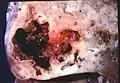

Pathology image of a lung abscess.